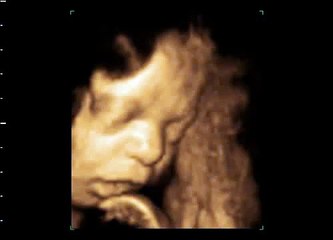

SPOT YOUR UNBORN LITTLE ONE GRIN IN THE MINDSET OF 3D ULTRASOUND SCANS

3D Ultrasound industry the sex of the baby is also determined ahead of with the normal 2D ultrasounds and lots of people find that knowing the sex will facilitate them to begin with the name as well as bond with the baby.